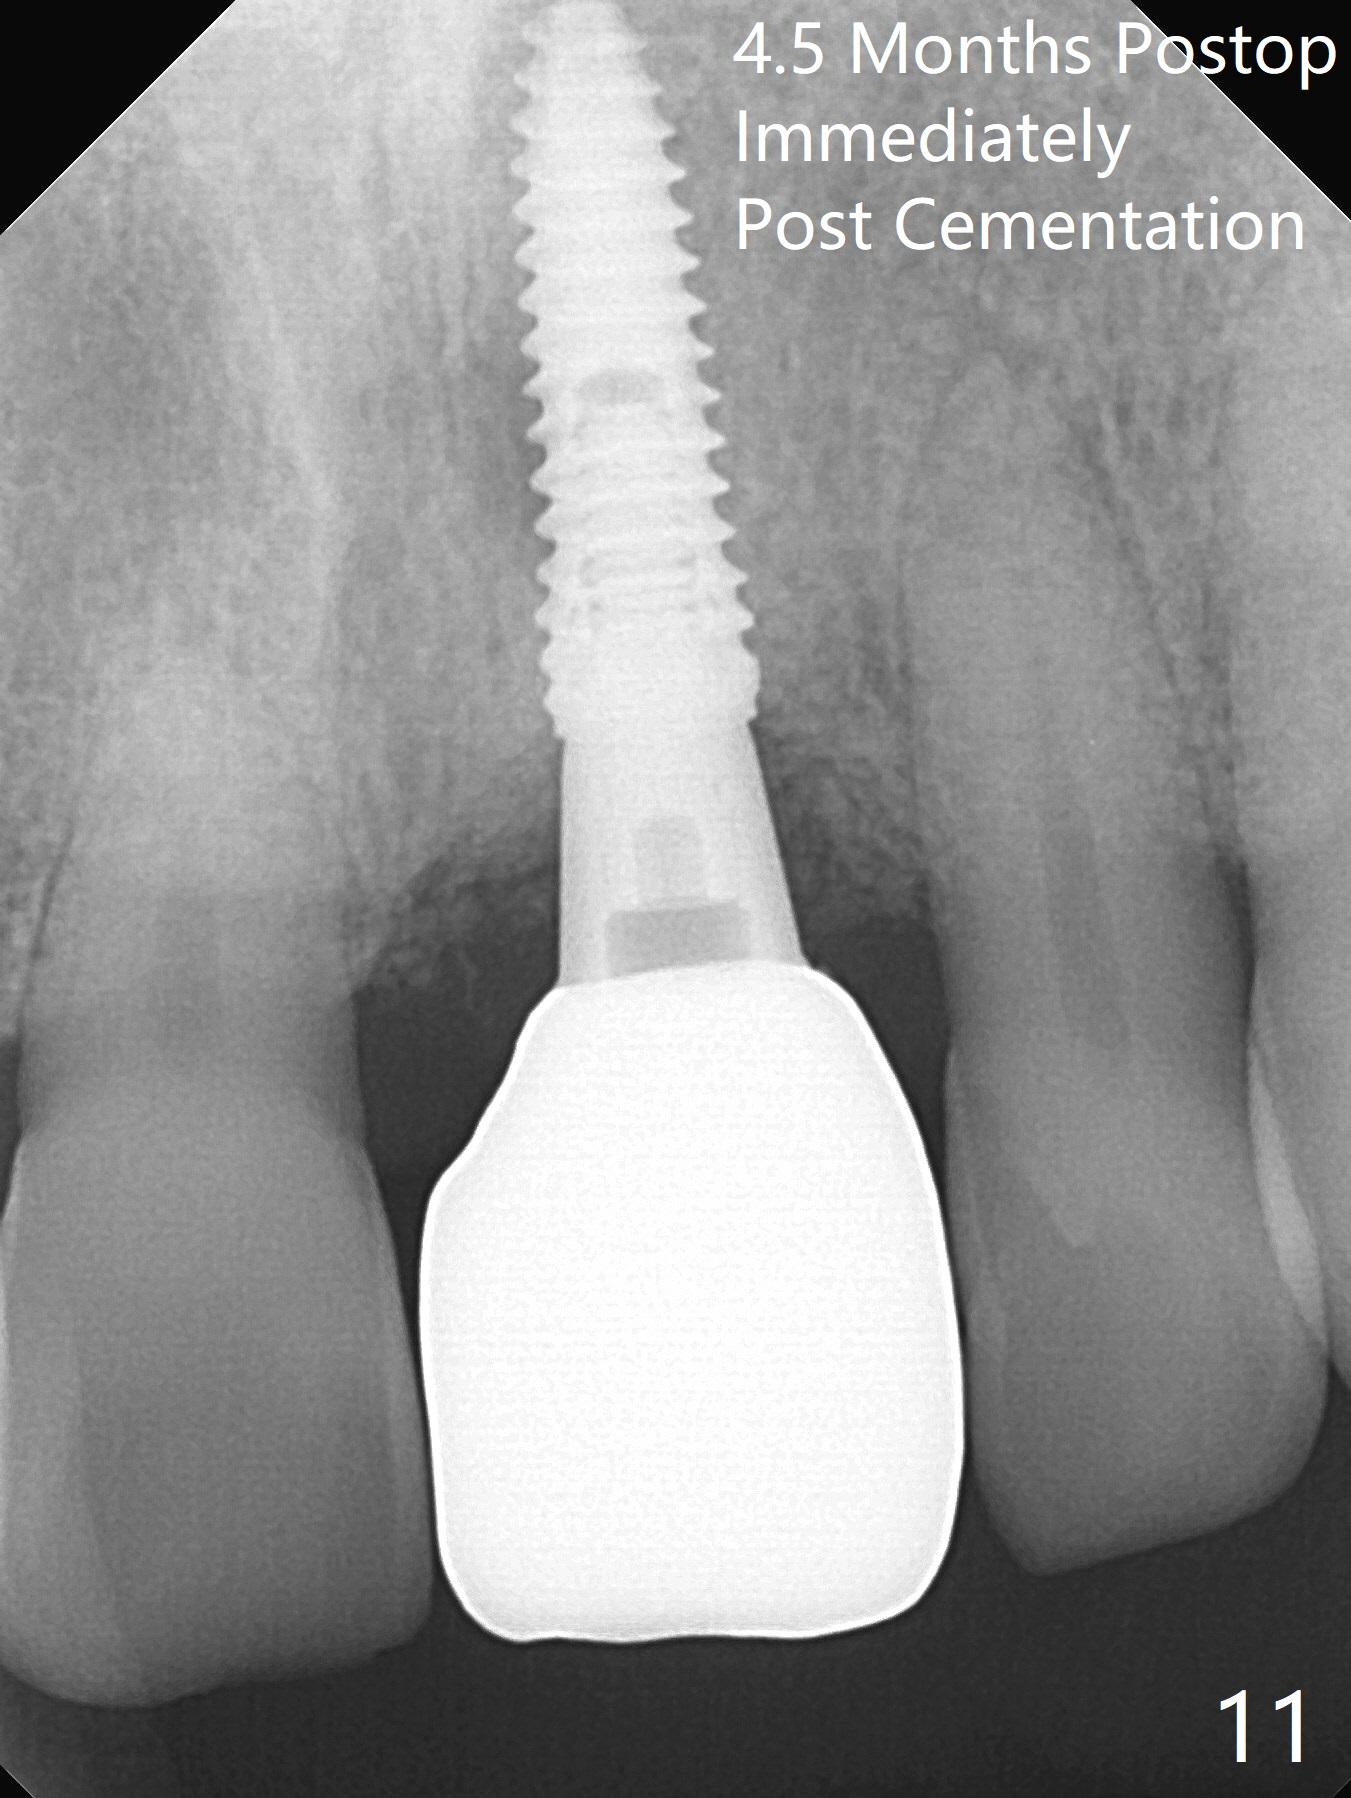

Preop examination shows mobility I of the teeth #8 and 10 and apparent occlusal trauma from #22-26 implant bridge. After occlusal equilibrium, incision reveals low, but moderate ridge at #9 (Fig.1). Fig.2a is a cross section of a normal upper incisor socket with thin buccal plate (B) and thick palatal one (P). It is difficult to initiate osteotomy in the oblique palatal wall when the buccal plate is resorbed (Fig.2b). In this case with horizontal buccal and palatal plate bone loss, the socket bottom is flat (Fig.2c), easy for osteotomy (Fig.2d green arrow, Fig.3). The initial osteotomy deviates mesial (Fig.3). To avoid perforation into the Incisive Canal, the trajectory is changed (Fig.4). After use of the final drill (3 mm), the coronal Incisive Canal is perforated. Following placement of a 3.5x13 mm implant and 4.5x5.5(4) mm abutment, Vanilla Graft is placed (Fig.5 *) to repair the perforation. Retrospectively, the coronal end of the Incisive Canal is revealed at incision (Fig.1 *). The initial osteotomy should be slightly more distal (Fig.3 black line). The buccal plate looks bulky due to placement of the abutment and bone graft 1 week postop (Fig.6,7 (crown dislodgement)). The bone graft appears to remain in place 2 months postop (Fig.8). Impression is taken because of instability of the immediate provisional (Fig.9 after Laser gingivectomy). The gingiva and buccal plate remain healthy 4.5 months postop (Fig.10). A permanent crown is cemented (Fig.11).